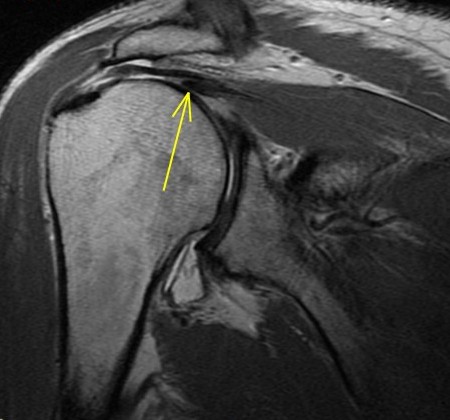

67 y/o with shoulder pain. Shoulder OA. R/O rotator Cuff tear.

The rotator cable is a collagenous thickening of the supraspinatus tendon which acts as a suspension bridge type mechanism strengthening its attachment. In my experience you dont see it in each case but in this case you see it well. Many supraspinatus tears involve the anterior aspect of the tendon and if severe enough can involve the cable and subscapularis tendon. Some consider it extending through the cable to involve the subscap. Biomechanically involvement of the cable can lead to weakness of supraspinatus function whereas if not involved the tear is said be “cresentic” and the patients usually have preserved strength – albeit are in pain. See the enclosed article. Reference article.

Supraspinatus and subscapularis tears involving the anterior rotator cable